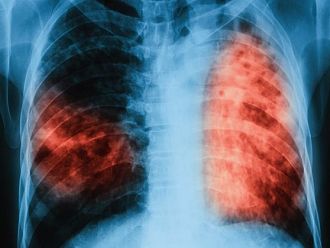

Над 78% от регистрираните пациенти са с туберкулоза на белия дроб. Над 59% от пациентите с белодробна туберкулоза отделят туберкулозни бацили и крият риск за околните контактни лица. През годините се запазва тенденция броят на мъжете да е над два пъти по-голям от броя на жените.